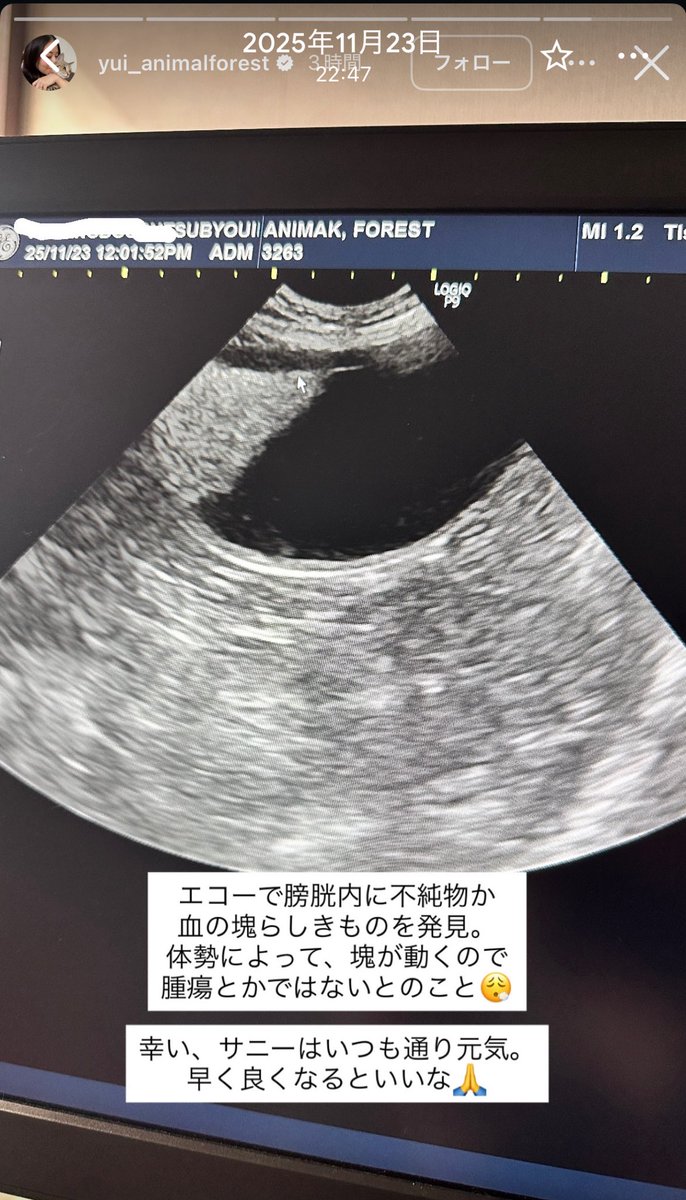

#アニマルフォレスト